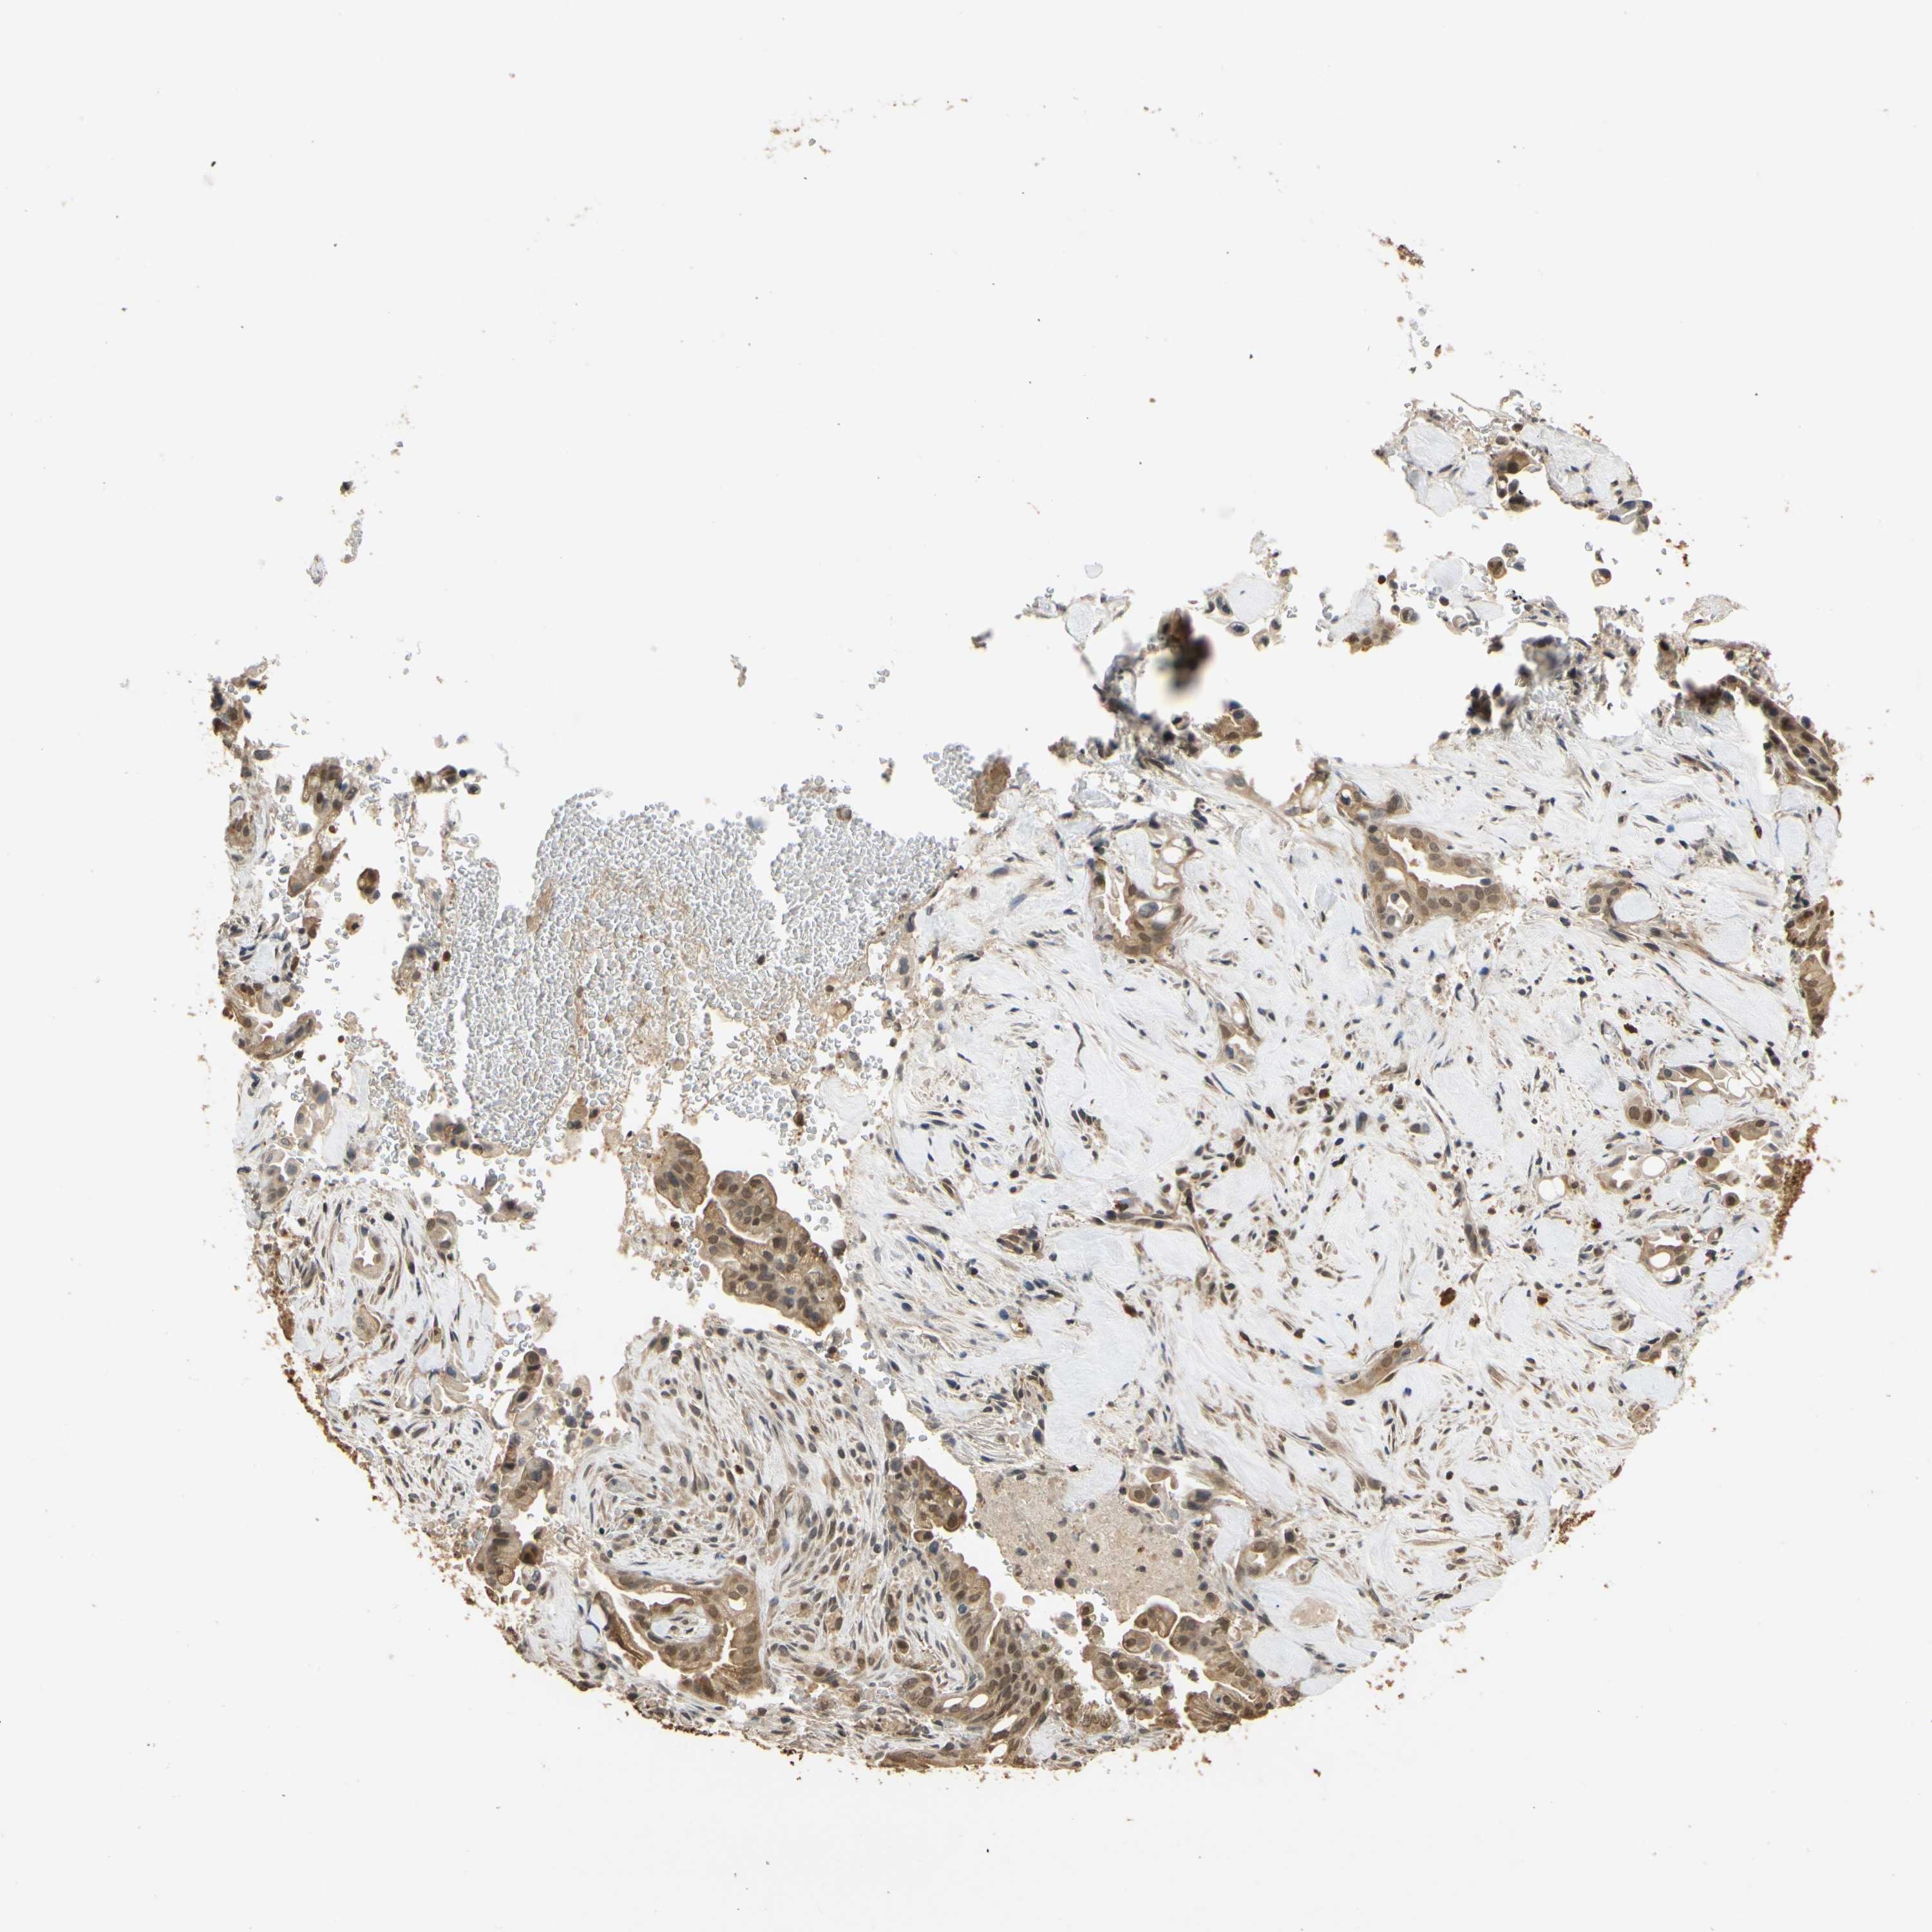

LIVER CANCER - Protein expressioni

A mouse-over function shows sample information and annotation data. Click on an image to view it in a full screen mode. Samples can be filtered based on level of antibody staining by selecting one or several of the following categories: high, medium, low and not detected. The assay and annotation is described here.

Note that samples used for immunohistochemistry by the Human Protein Atlas do not correspond to samples in the TCGA dataset.

Antibody stainingi

Antibody staining in the annotated cell types in the current human tissue is reported as not detected, low, medium, or high, based on conventional immunohistochemistry profiling in selected tissues. This score is based on the combination of the staining intensity and fraction of stained cells.

Each image is clickable and will lead to virtual microscopy that enables deeper exploration of all samples and also displays staining intensity scores, fraction scores and subcellular localization as well as patient and tissue information for each sample.

Antibody HPA001401

Antibody CAB008670

Staining

High

Medium

Low

Not detected

Intensity

Strong

Moderate

Weak

Negative

Quantity

>75%

75%-25%

<25%

None

Location

Nuclear

Cytoplasmic/membranous

Cytoplasmic/membranous,nuclear

Carcinoma, Hepatocellular, NOS

Cholangiocarcinoma